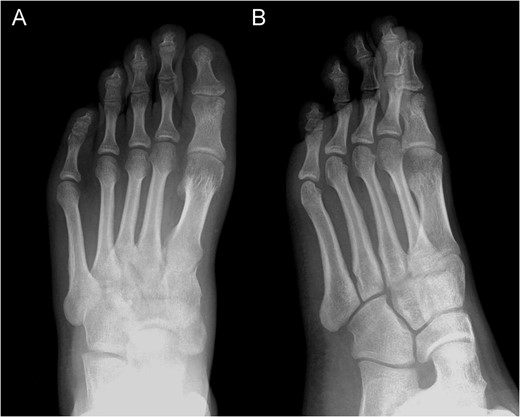

Posterior–anterior (A) and lateral (B) X-ray imaging of the left foot, showing the arthrodesis without signs of recurrence after a follow-up of 30 months.

The pain decreased post operation with no rest-pain after 3 weeks. After 6 weeks, the X-ray revealed radiological signs of consolidation which allowed for weight bearing. Four months after surgery, the patient returned to sport without limitations.